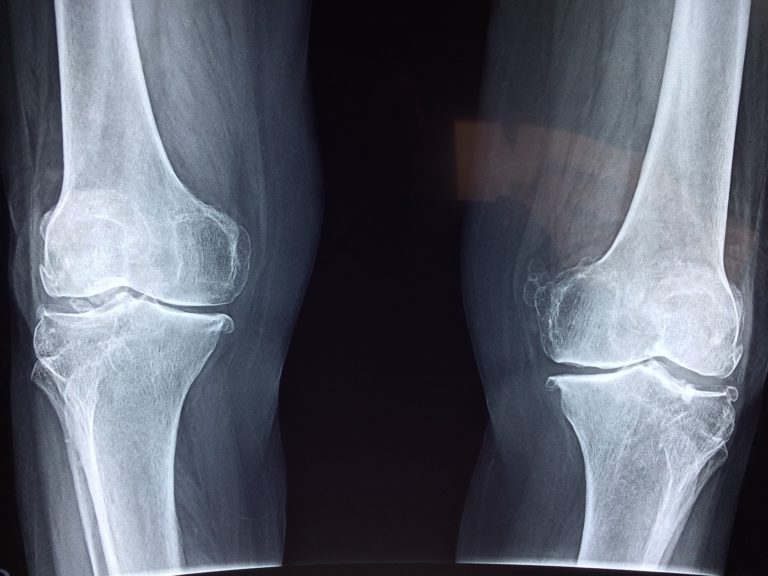

Opuchnięte kolano może wskazywać na różne problemy, zawsze wymagające konsultacji lekarskiej, jeśli stan się utrzymuje lub pogarsza. Oto mój sprawdzony domowy przepis na ból, obrzęk, a nawet wodę w kolanie.